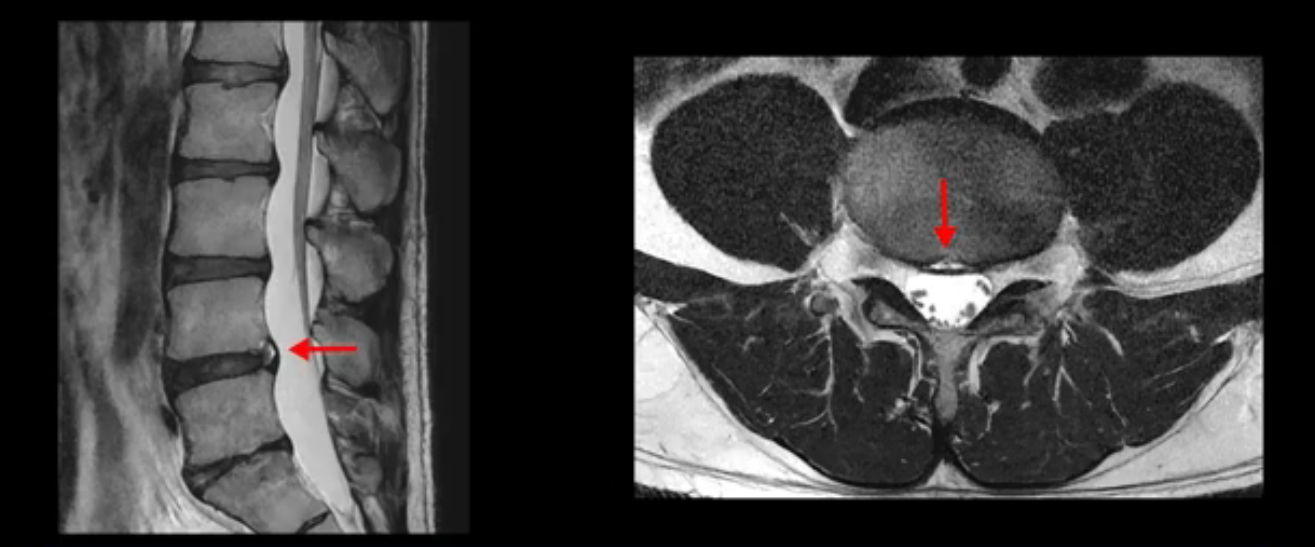

우선 이분 MRI를 보면 허리 모든 마디의 디스크가 퇴행되어 있고

여러 마디의 디스크가 조금씩 밀려나와 보이고, 디스크 섬유륜도 찢어져 보이는 마디도 보입니다.

그런데 이분의 증상과 MRI가 전혀 일치하지 않는데, 왜 그런지 지금부터 자세히 설명드립니다. 이분 증상은 앉으면 엉치와 허리가 심하게 아파 10분 이상 앉는 게 어렵고 양쪽 발가락이 앉아있을 때나 누워있을 때 다 저립니다. 걸을 때도 아파서 10분 걷기도 어렵습니다. MRI를 마디마디 살펴보면 1번 2번은 오른쪽으로 살짝 밀려나온 디스크가 있지만 전혀 심하지 않고, 뒤에 또 설명하겠지만 최근에 밀려나온 급성 디스크가 아니고 오래된 디스크로 판단됩니다.

2번 3번도 비교적 디스크 상태는 좋고 신경 구멍 넓이도 아주 넓습니다.

3번 4번도 마찬가지로 디스크상태 좋아 보이고 신경 눌림 전혀 없어 보입니다.

4번 5번은 가운데로 섬유륜이 찢어져서 디스크가 살짝 밀려나와 있지만 역시나 최근에 찢어지고 밀려나온 걸로 판단되지 않고 오래 전에 찢어진 흔적으로 보입니다.

왜 최근에 찢어진 급성이 아니고 오래된 거라고 하는지 이 부분도 뒤에 한꺼번에 설명 드리겠습니다.

5번 1번 역시 가운데로 디스크 조금 밀려 나와있지만 신경 공간 넓이는 아주 넓어서 신경 눌림 있을 거라고 예상이 안됩니다.

추간공도 보시다시피 왼쪽, 오른쪽 전부 다 매우 넓어서 신경이 눌릴만한 부분이 전혀 보이지 않습니다.

앞서 1번 2번, 4번 5번, 5번 1번의 디스크가 찢어지고 조금 밀려 나온 게 최근에 찢어진 게 아니고 오래된 걸로 보인다고 말씀 드렸죠. 왜 그럴까요? 만약 급성으로 찢어진 것이라면 아주 심한 디스크성 통증이 있겠죠. 기침이나 재채기를 하면 심하게 아프고 허리를 조금만 구부리거나 비틀면 아주 날카로운 통증들이 생길 겁니다. 그런데 이분은 이런 증상이 전혀 아닙니다. 또 디스크의 밀려나온 정도도 전혀 심하지 않기 때문에 이분이 가지고 계신 양쪽 다리 저림, 특히 이분은 누워있을 때도 양쪽 발이 발가락까지 쑤신다고 하는데 이정도 디스크 때문에 그런 증상은 생길 수가 없는 겁니다. 이처럼 이분의 가벼운 디스크 탈출은 이미 오래 전에 진행되었고 섬유륜 자체는 이미 아문 상태인데도 디스크내장증을 진단받은 환자들 중에는 본인이 섬유륜 파열 환자라고 끝까지 믿는 분들이 많습니다. 다시 말하지만 디스크내장증이라는 진단을 받은 환자들을 보면 거의 전부 다 섬유륜 파열 증상이 아닙니다. 증상이 완전히 다릅니다. 진단이 애초에 잘못되면 어떤 치료를 받아도 좋아질 수 없습니다.

이분은 어떤 한 병원에서 디스크 내장증 얘기를 들으셨는데요. 여기 보시는 것처럼 4번 5번의 하얀 HIZ(High Intensity Zone)을 보고 디스크 내장증의 근거로 얘기하는 병원들이 있는데,

이 HIZ는 섬유륜이 찢어졌다가 이미 아문 뒤에도 얼마든지 보일 수 있는 흔적일 가능성이 있어서 재채기를 하면 아픈지, 허리를 구부릴 때 날카로운 통증이 생기는가 등의 증상으로 구별해야 하는데 MRI만 보고 HIZ가 보이면 그게 마치 통증의 원인인 것처럼 얘기하는 의사들이 있습니다. 이분 MRI를 자세히 보고 증상을 정말 자세히 들어본 의사가 있었더라면 다른 환자분들처럼 증상과 MRI가 일치하지 않는다는 얘기를 들을 수 있었을 텐데 이분은 그런 얘기는 듣지 못했습니다.